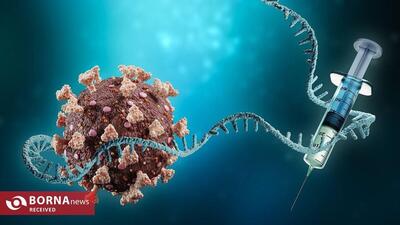

انقلاب در درمان سرطان ریه/ واکسن BNT116 وارد میدان شد!

شرکت بیونتک به رهبری اوگور شاهین، واکسن جدید BNT116 را با فناوری mRNA برای درمان سرطان ریه وارد مرحله آزمایش بالینی کرده است.